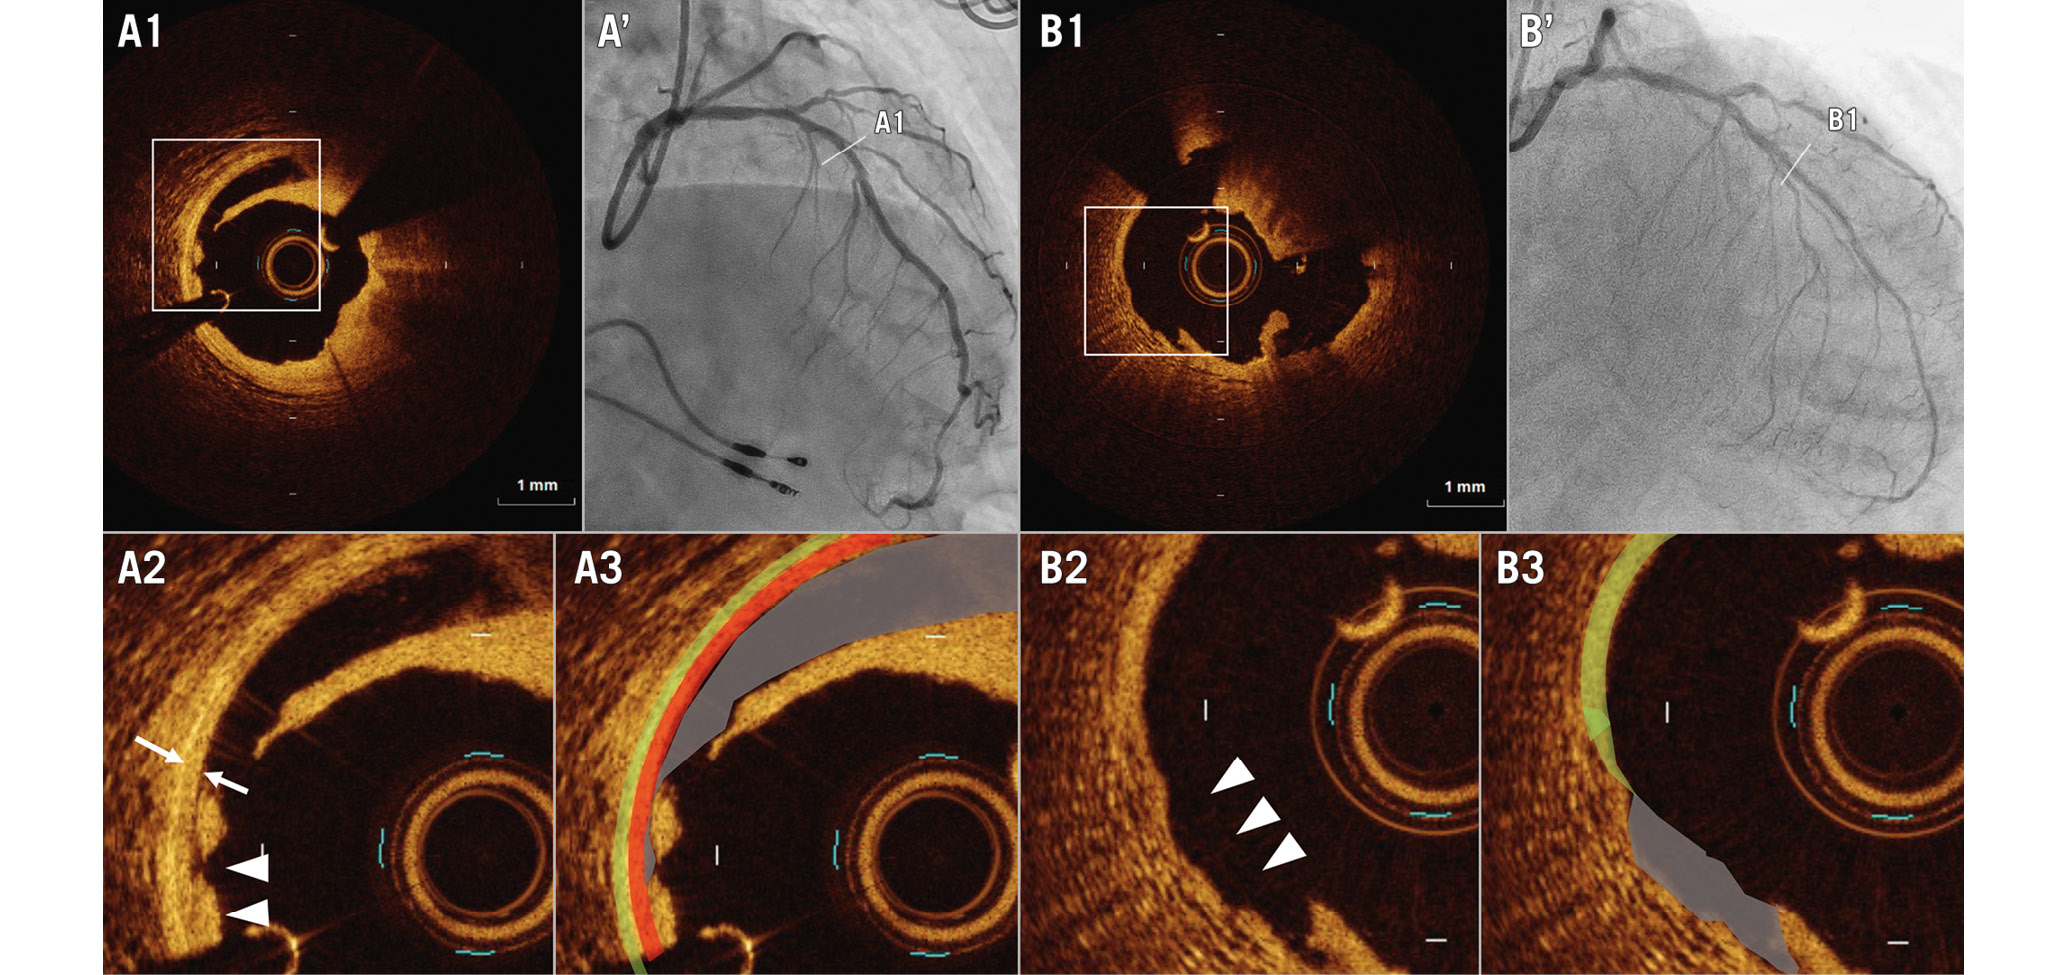

We evaluated pre- and post-PCI OCT images quantitatively and qualitatively. At pre-PCI OCT, calcium was defined as a signal-poor or heterogeneous region with a sharply delineated border. The maximum arc of target lesion calcium was measured in degrees with a protractor centred on the lumen. The maximum calcium thickness was also measured14. A calcified nodule was defined as an accumulation of small calcium deposits underlying a calcified plaque, which included either a pathological eruptive calcified nodule or nodular calcification715. At post-PCI OCT, we assessed the final minimum lumen area and the presence or absence of coronary artery dissections16. The axial injury of the dissection was described as intimal dissection when only the intima was affected and the media was still intact, as medial dissection when the dissection extended into the media without disruption of the entire medial layer, and as adventitial dissection when the media was dissected throughout its thickness (Figure 1). In addition, the maximum dissection angle and longitudinal dissection length were assessed.

Figure 1. Representative images of medial and adventitial involvement of coronary artery dissection and injury. A1-3) Post-percutaneous coronary intervention (PCI) optical coherence tomography (OCT) images of medial involvement of the coronary artery dissection and injury. The double arrows indicate the media, while the arrowheads indicate medial involvement of the coronary artery dissection and injury. Medial dissection (grey), media (red), and adventitia (light green). A’) Post-PCI coronary angiogram corresponding to OCT images A1-3. B1-3) Post-PCI OCT images of adventitial involvement of the coronary artery dissection and injury. The arrowheads indicate the point of adventitial involvement of the coronary artery dissection and injury. The adventitia (light green) disappears at the dissection and injury segment (grey). B’) Post-PCI coronary angiogram corresponding to OCT images B1-3.